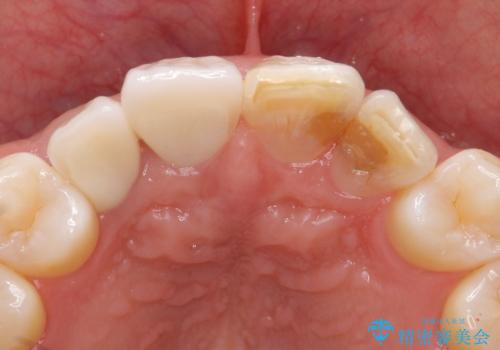

仕上がりに限界はありましたが、比較的短期間で歯並びが整いセラミック治療を行うことができ、患者様に「治療して良かった」とご満足頂けました。

左上1の歯の表面にもともと凹凸とグラデーションがあり、気になるようならセラミックでかぶせるのも一つだと提案しましたがご希望されなかったため、その表面性状を再現して右上1のセラミッククラウンを作製しています。

右上21:ジルコニアクラウン スペシャル